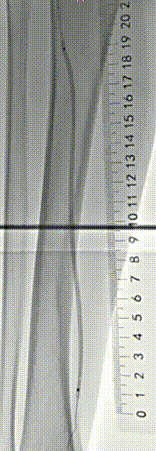

经过周密的术前评估(结合下肢动脉 CTA、ABI 血管功能检测)和多轮讨论后,血管外科姜坤主任团队为李大爷开展微创介入手术,全程在影像引导下精准推进:

▲术前血管造影与CTA相符

▲采用导丝通过支架内闭塞段顺利,考虑为内膜增生合并部分陈旧性血栓病变,再次造影明确病变长度。

▲血管斑块旋切系统逐段旋切抽吸病变段。

▲造影提示治疗效果良好,成功开通闭塞段。

▲Blades Up模式再次抽吸病变段,股腘动脉管腔获得满意,膝下胫后动脉、足部血流灌注同前,未见明显栓塞。

▲股浅、腘、胫后动脉经POBA+5*300 先瑞达DCB球囊扩张。

▲治疗完毕,最终造影结果,股浅动脉局部非限流性夹层,支架内、膝下流出道血流速满意。